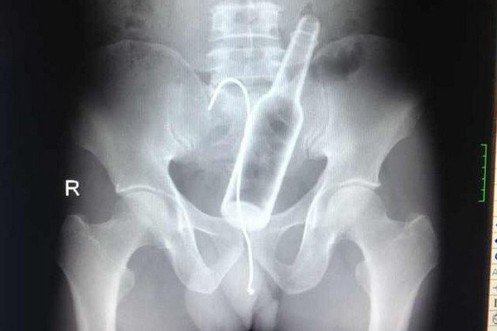

Shot-Glas, Spraydose und so

Spannende Statistik: Letztes Jahr haben wir folgende Sachen rektal eingeführt ...